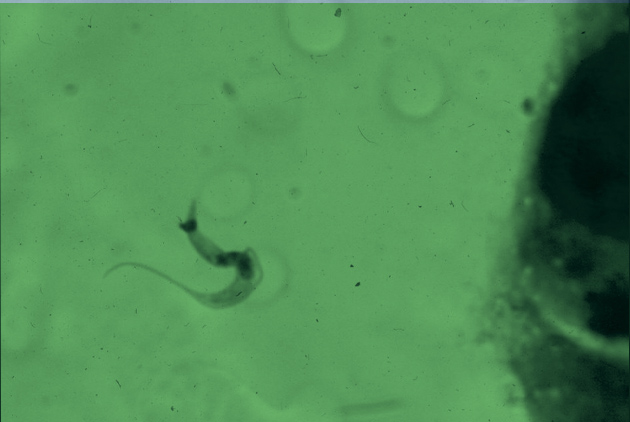

Departamento Departamento de Parasitología

• Galería de Imágenes y Material Audiovisual

• Galería de Imágenes